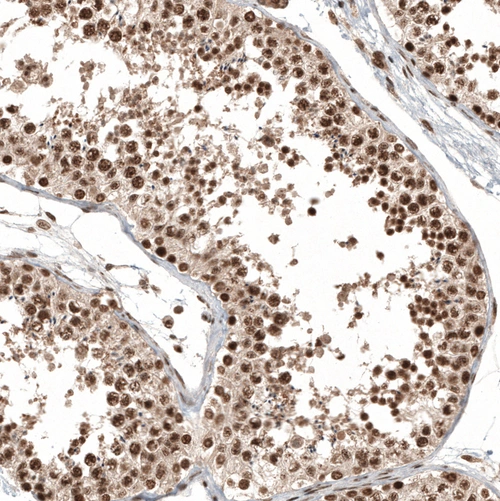

Immunohistochemical staining of human testis shows strong nuclear positivity in cells in seminiferous ducts.